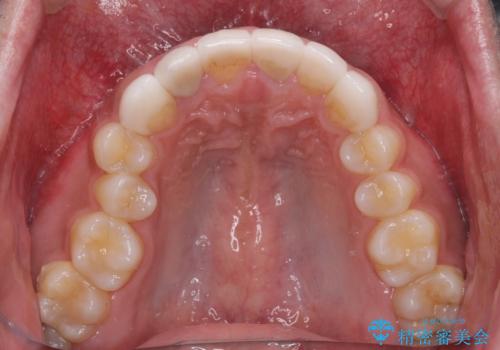

- 前歯のセラミッククラウンが欠けてしまったとのことで来院された患者様です。

周りの他の歯もセラミッククラウンやラミネートベニアが装着されていたため、欠けてしまったクラウンを丁寧に取り外し、同じような色合いとなるように製作することとしました。

欠けたセラミッククラウンを丁寧に外して技工所に送ったことで、元のセラミッククラウン同様の色合いとなり、自然な仕上がりとなりました。